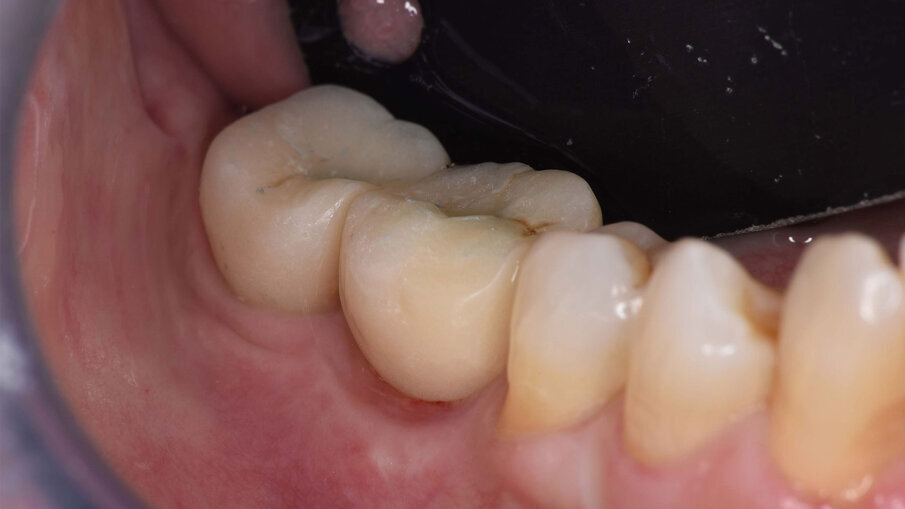

Dopo due settimane, è stata eseguita una scansione 3D con scan body e sono state consegnate due corone provvisorie avvitate sugli impianti, in modo da poter condizionare i tessuti molli peri-implantari (Figg. 11-12b). A causa di un’inadeguata banda di mucosa cheratinizzata sul versante vestibolare, è stato eseguito un intervento di vestiboloplastica con affondamento di fornice e innesto epitelio-connettivale prelevato dal palato (Figg. 13, 14). Dopo un’ulteriore maturazione dei tessuti, una nuova scansione ha permesso di dare informazioni all’odontotecnico circa il tragitto transmucoso ottenuto con i provvisori e sono state consegnate due corone definitive avvitate in zirconio (odt. Alessandro Giacometti; Figg. 15-19b). La paziente è stata seguita con controlli periodici clinici e radiografici a 6 mesi, 1 anno e 2 anni dal carico protesico (Figg. 20a, 20b).

Figg. 19a, 19b_Immagine clinica e radiografica che mostrano il manufatto protesico finale.